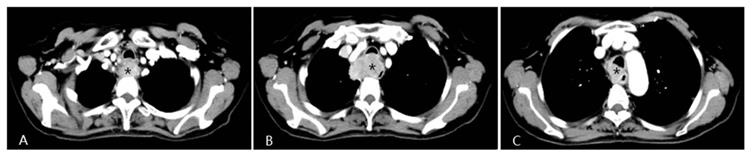

Fig 1

A patient with progressive dysphagia for 2 months was diagnosed with esophageal squamous cell cancer via endoscopic biopsy. Due to her poor condition, the oncologists did not recommend systemic chemotherapy, but instead suggested arterial infusion chemotherapy. Chest CT shows an apparently enhanced mass (*) in the middle-upper esophagus with moderate stenosis of the tracheal cavity due to tumor invasion.

Fig 3

Four weeks after interventional therapy, a chest CT scan shows that the lesion has significantly reduced, tracheal lumen is normal, and the arterial phase enhancement is not apparent (*) (A, B, C).